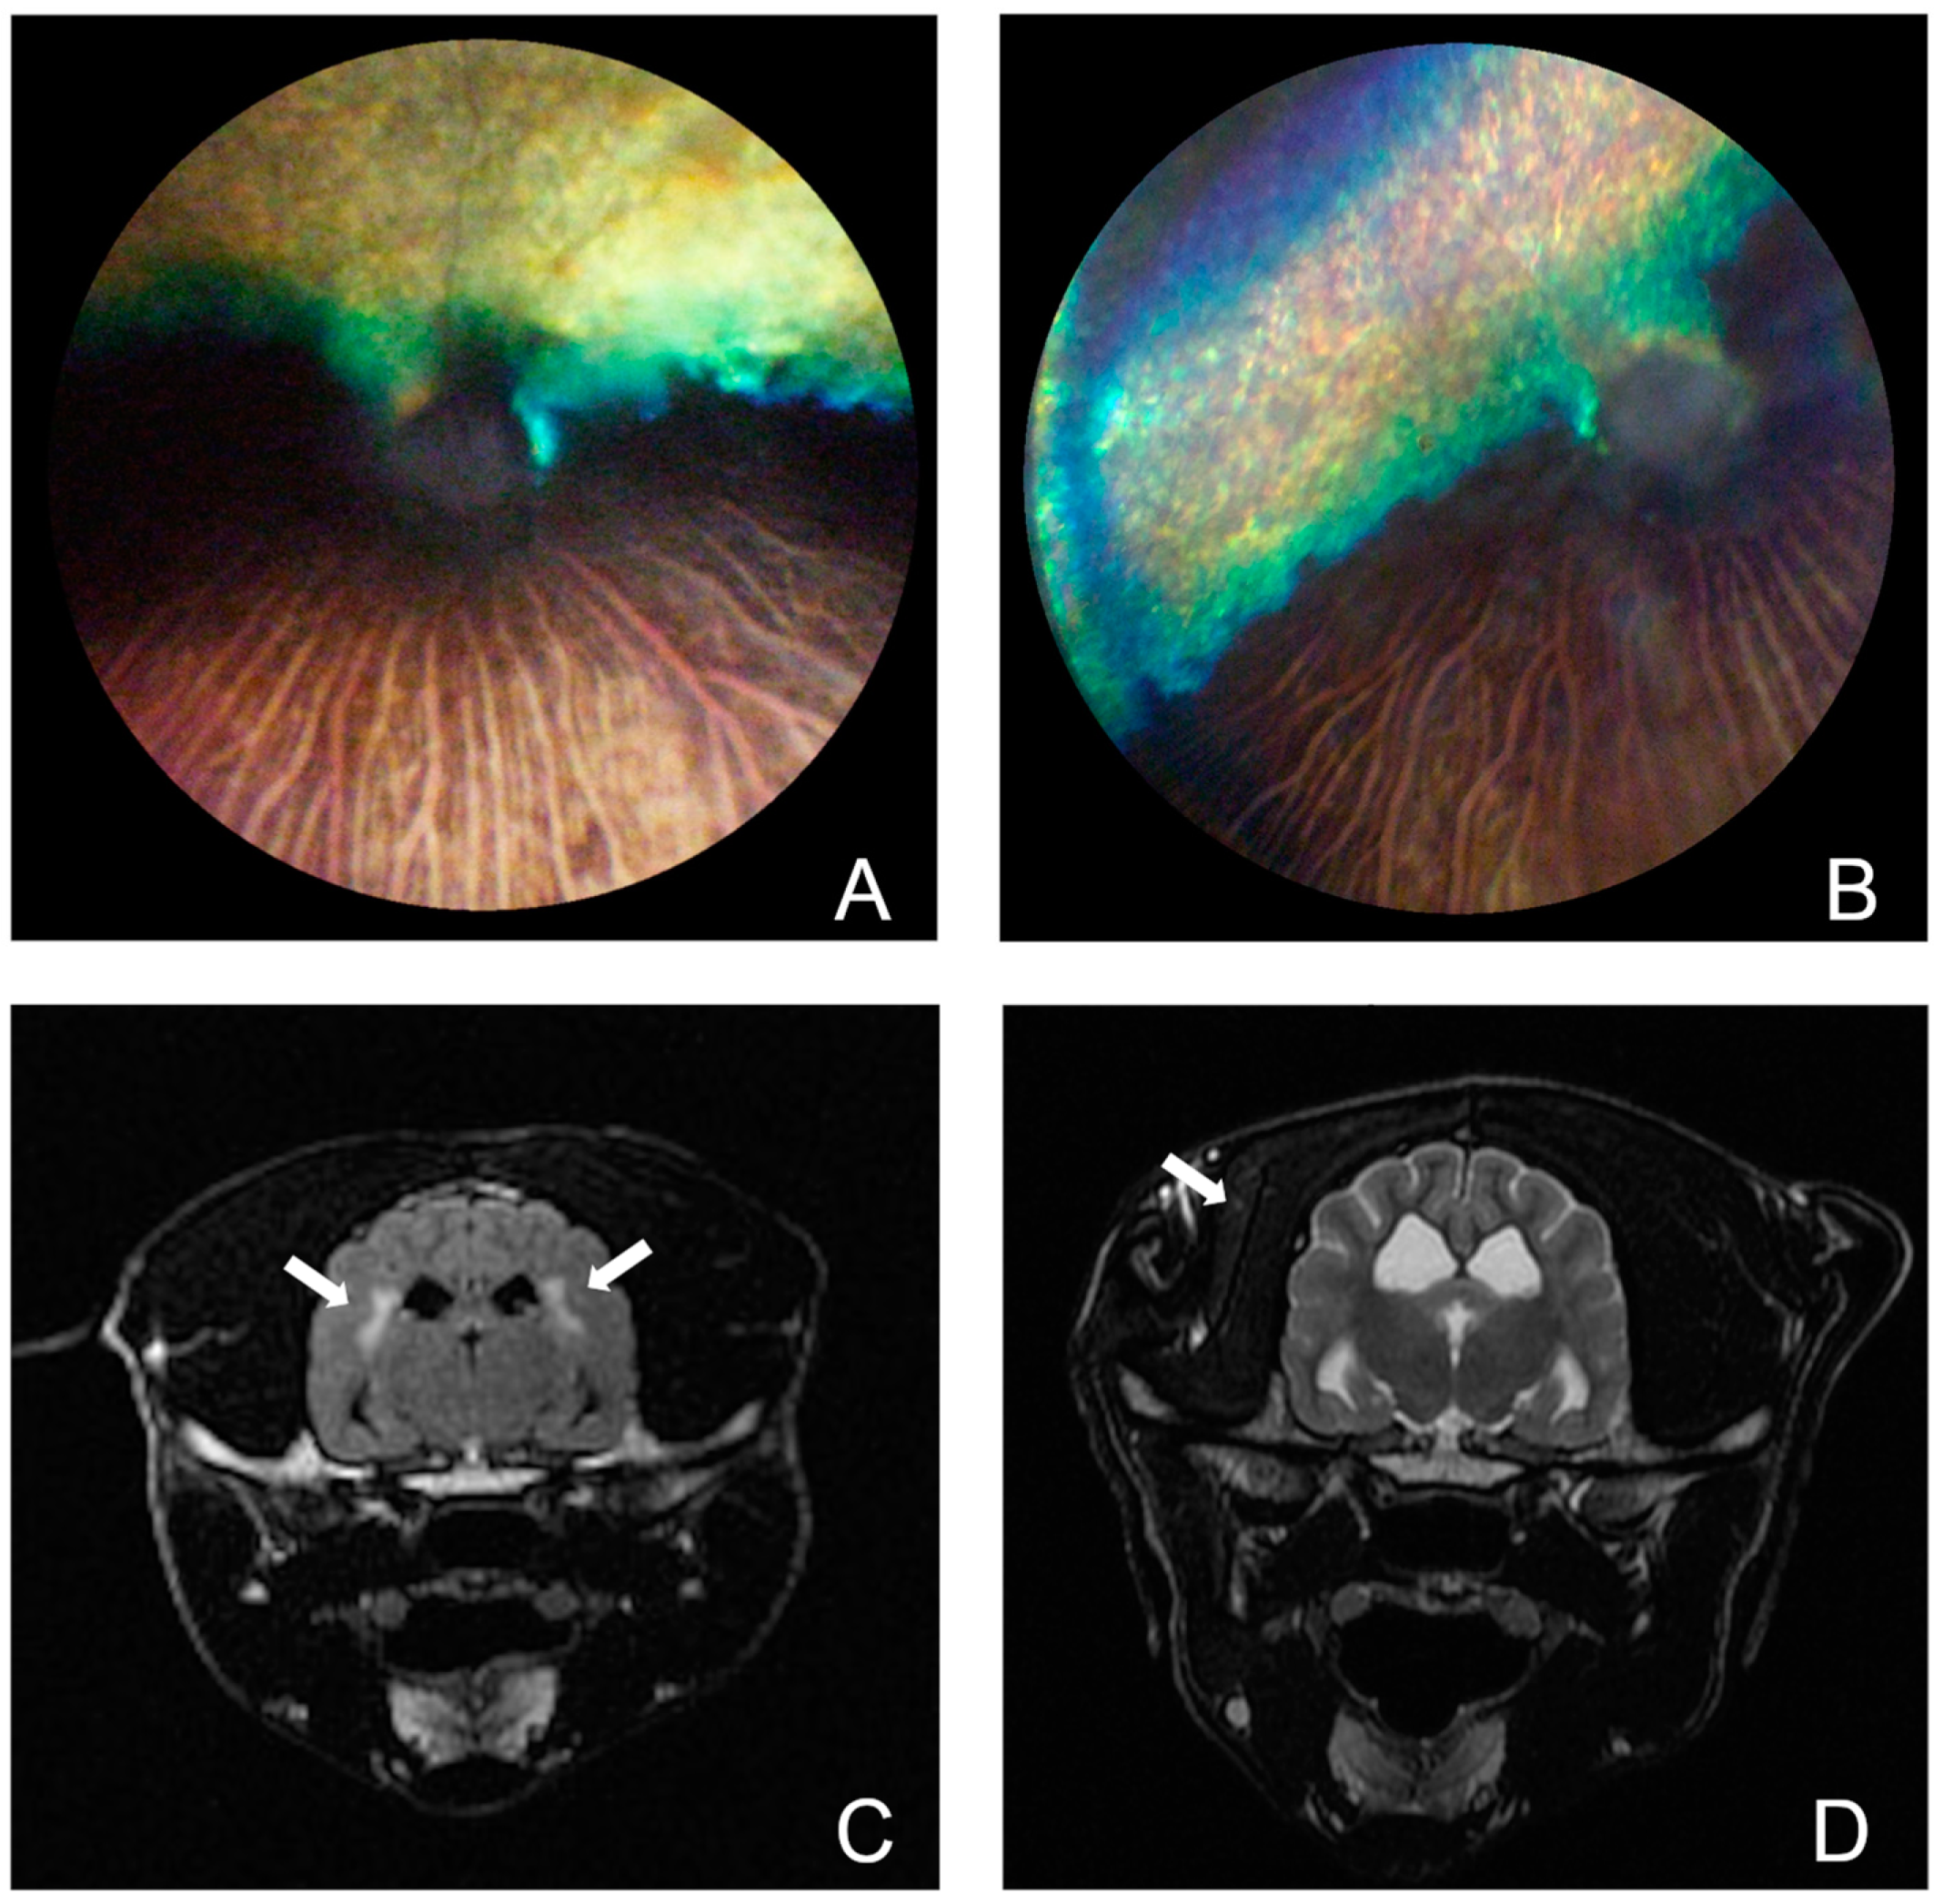

3.1. Phenotype Characterization